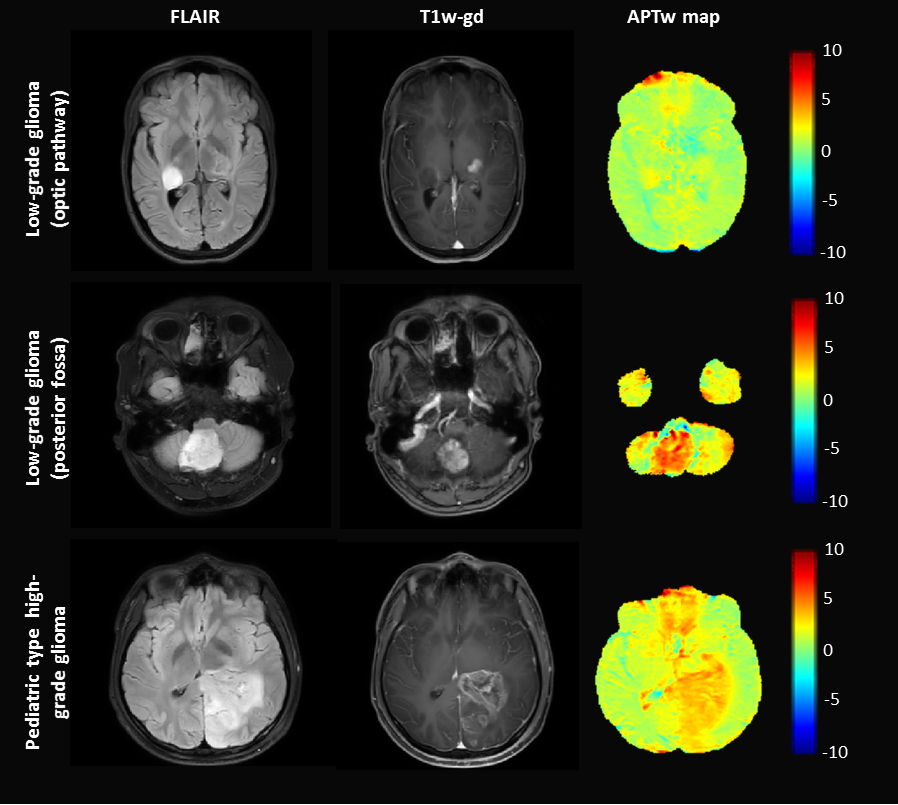

APTw values are higher in tumor compared to NAWM for both low-grade and high-grade types of pediatric brain tumors(p<0.001)(Fig.2 and Fig.3). No significant differences were found in APTw values between low-grade and high-grade glioma(p=0.23). MTRasym with fluid suppression suppressed cystic fluids in pediatric brain tumors (Fig.4).

Figure 2: Three examples of APTw imaging and correlated anatomical scans of different pediatric brain tumors. Pilocytic astrocytoma located in the optic pathway showing slightly higher APTw values compared to NAWM; Pilocytic astrocytoma located in the posterior fossa with BRAF- GNAI1 fusion, showing high APTw values; Pediatric type high-grade glioma (diffuse hemispheric glioma) with H3 G34 mutation, showing high APTw values.